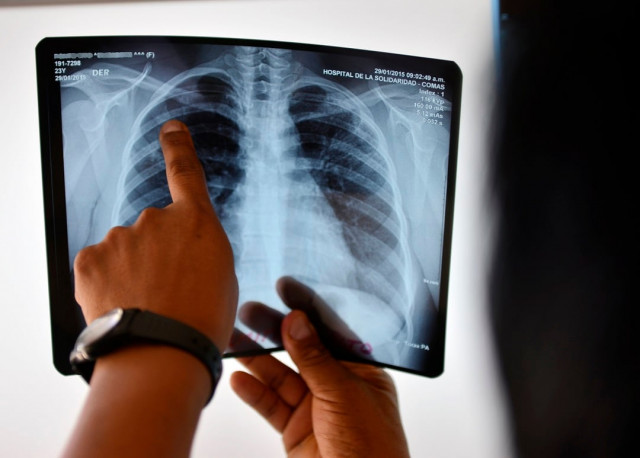

Tuberculosis, which is preventable and curable, is caused by bacteria that most commonly affect the lungs. It is spread through the air when people with TB cough, sneeze or spit.